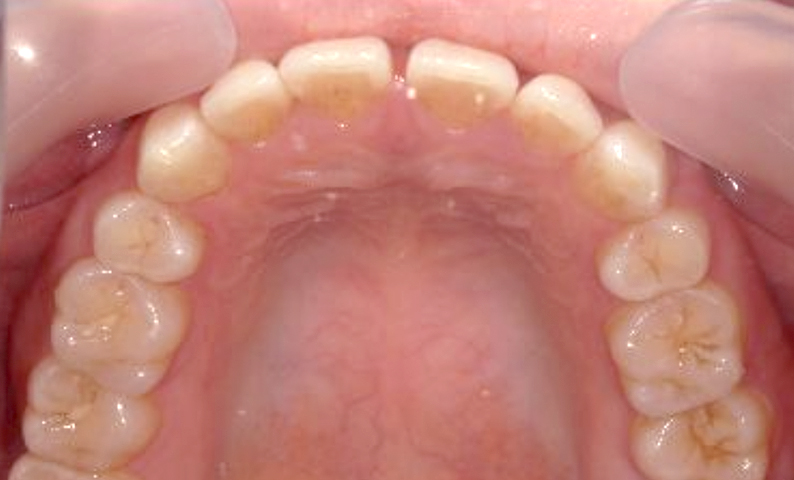

| 治療前 | 治療後 |

|---|---|

|